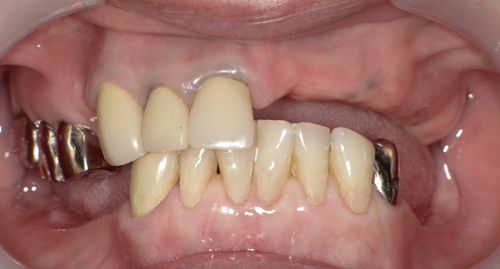

左下のインプラント予定部。

切開して開けてみると、2ヶ月前の抜歯跡が見受けられた。しかし

当院では骨の再生治療をインプラント移植時に同時進行で施しているので、全く問題はありません。

骨のない所に人工骨のβ–TCPを添加して、本物の骨に置換するのを待ちます。

左下の施術終了。